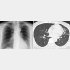

咳や痰が続きつらいなら疑うべき…「気管支拡張症」とは?

50代女性。胸部X線写真(左)では見落とされやすいが、CT(右)では明らか(徳田医師提供)